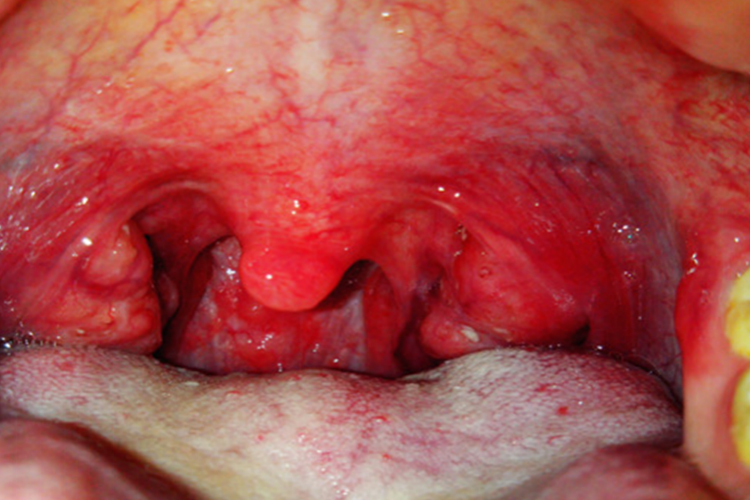

儿童急性咽喉炎可累及整个咽喉部,导致咽喉充血、灼热、有疼痛感,声音嘶哑或声音粗糙,可见咽部发红、肿胀、吞咽困难、颈部淋巴结肿大、发热等症状,慢性咽喉炎多表现为咽喉不适感,如咽喉轻度红肿、咽干、咽痒、刺激性干咳等;

儿童患急性扁桃体炎可引起咽喉发红、声音嘶哑、咽痛、咳嗽、咳痰、下颌下淋巴结肿大、吞咽困难等局部症状,还可出现畏寒、高热、头痛、食欲不振、四肢无力、酸痛等全身症状。

慢性扁桃体炎发作时也可引起咽喉红肿、发干、发痒、异物感、刺激性咳嗽等症状,少数可引起消化不良、头痛乏力、低热表现。